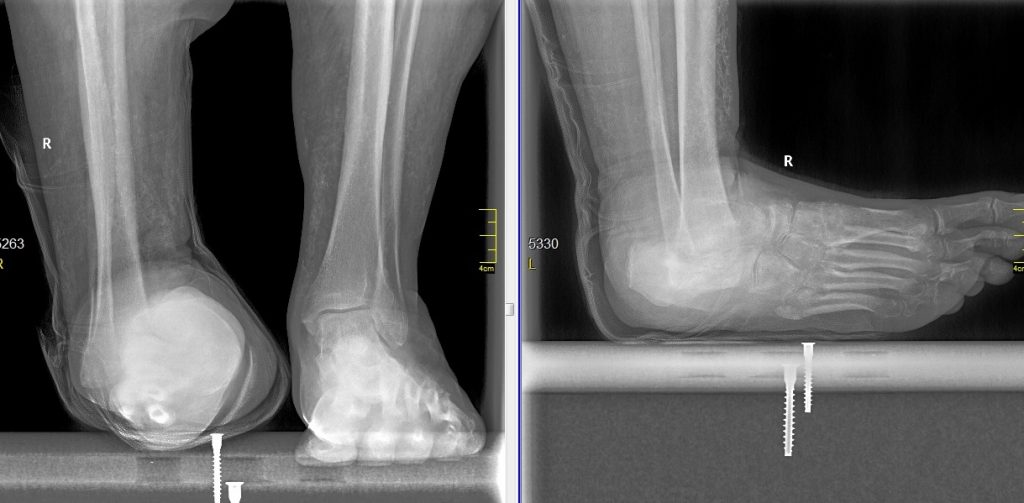

Алексей Р. из Ижевска обратился к врачам травматолого-ортопедического отделения №5 (хирургия стопы и голеностопного сустава) Новосибирского НИИТО им. Я.Л. Цивьяна Минздрава России по поводу тяжёлой деформации стопы, которая развилась на фоне асептического некроза таранной кости и ультравысокой массы тела (около 200 килограммов при росте 190 сантиметров).

К 48 годам таранная кость мужчины частично была раздавлена, возникла трофическая язва, и Алексей испытывал невыносимую боль при ходьбе. Надевание и ношение обуви стало невозможным.

Операция по коррекции деформации, включающая артродез и внутреннюю фиксацию металлической конструкцией, прошла успешно.